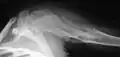

X-ray showing enchondromas localized in the humerus of a 37-year-old patient affected with Ollier disease -